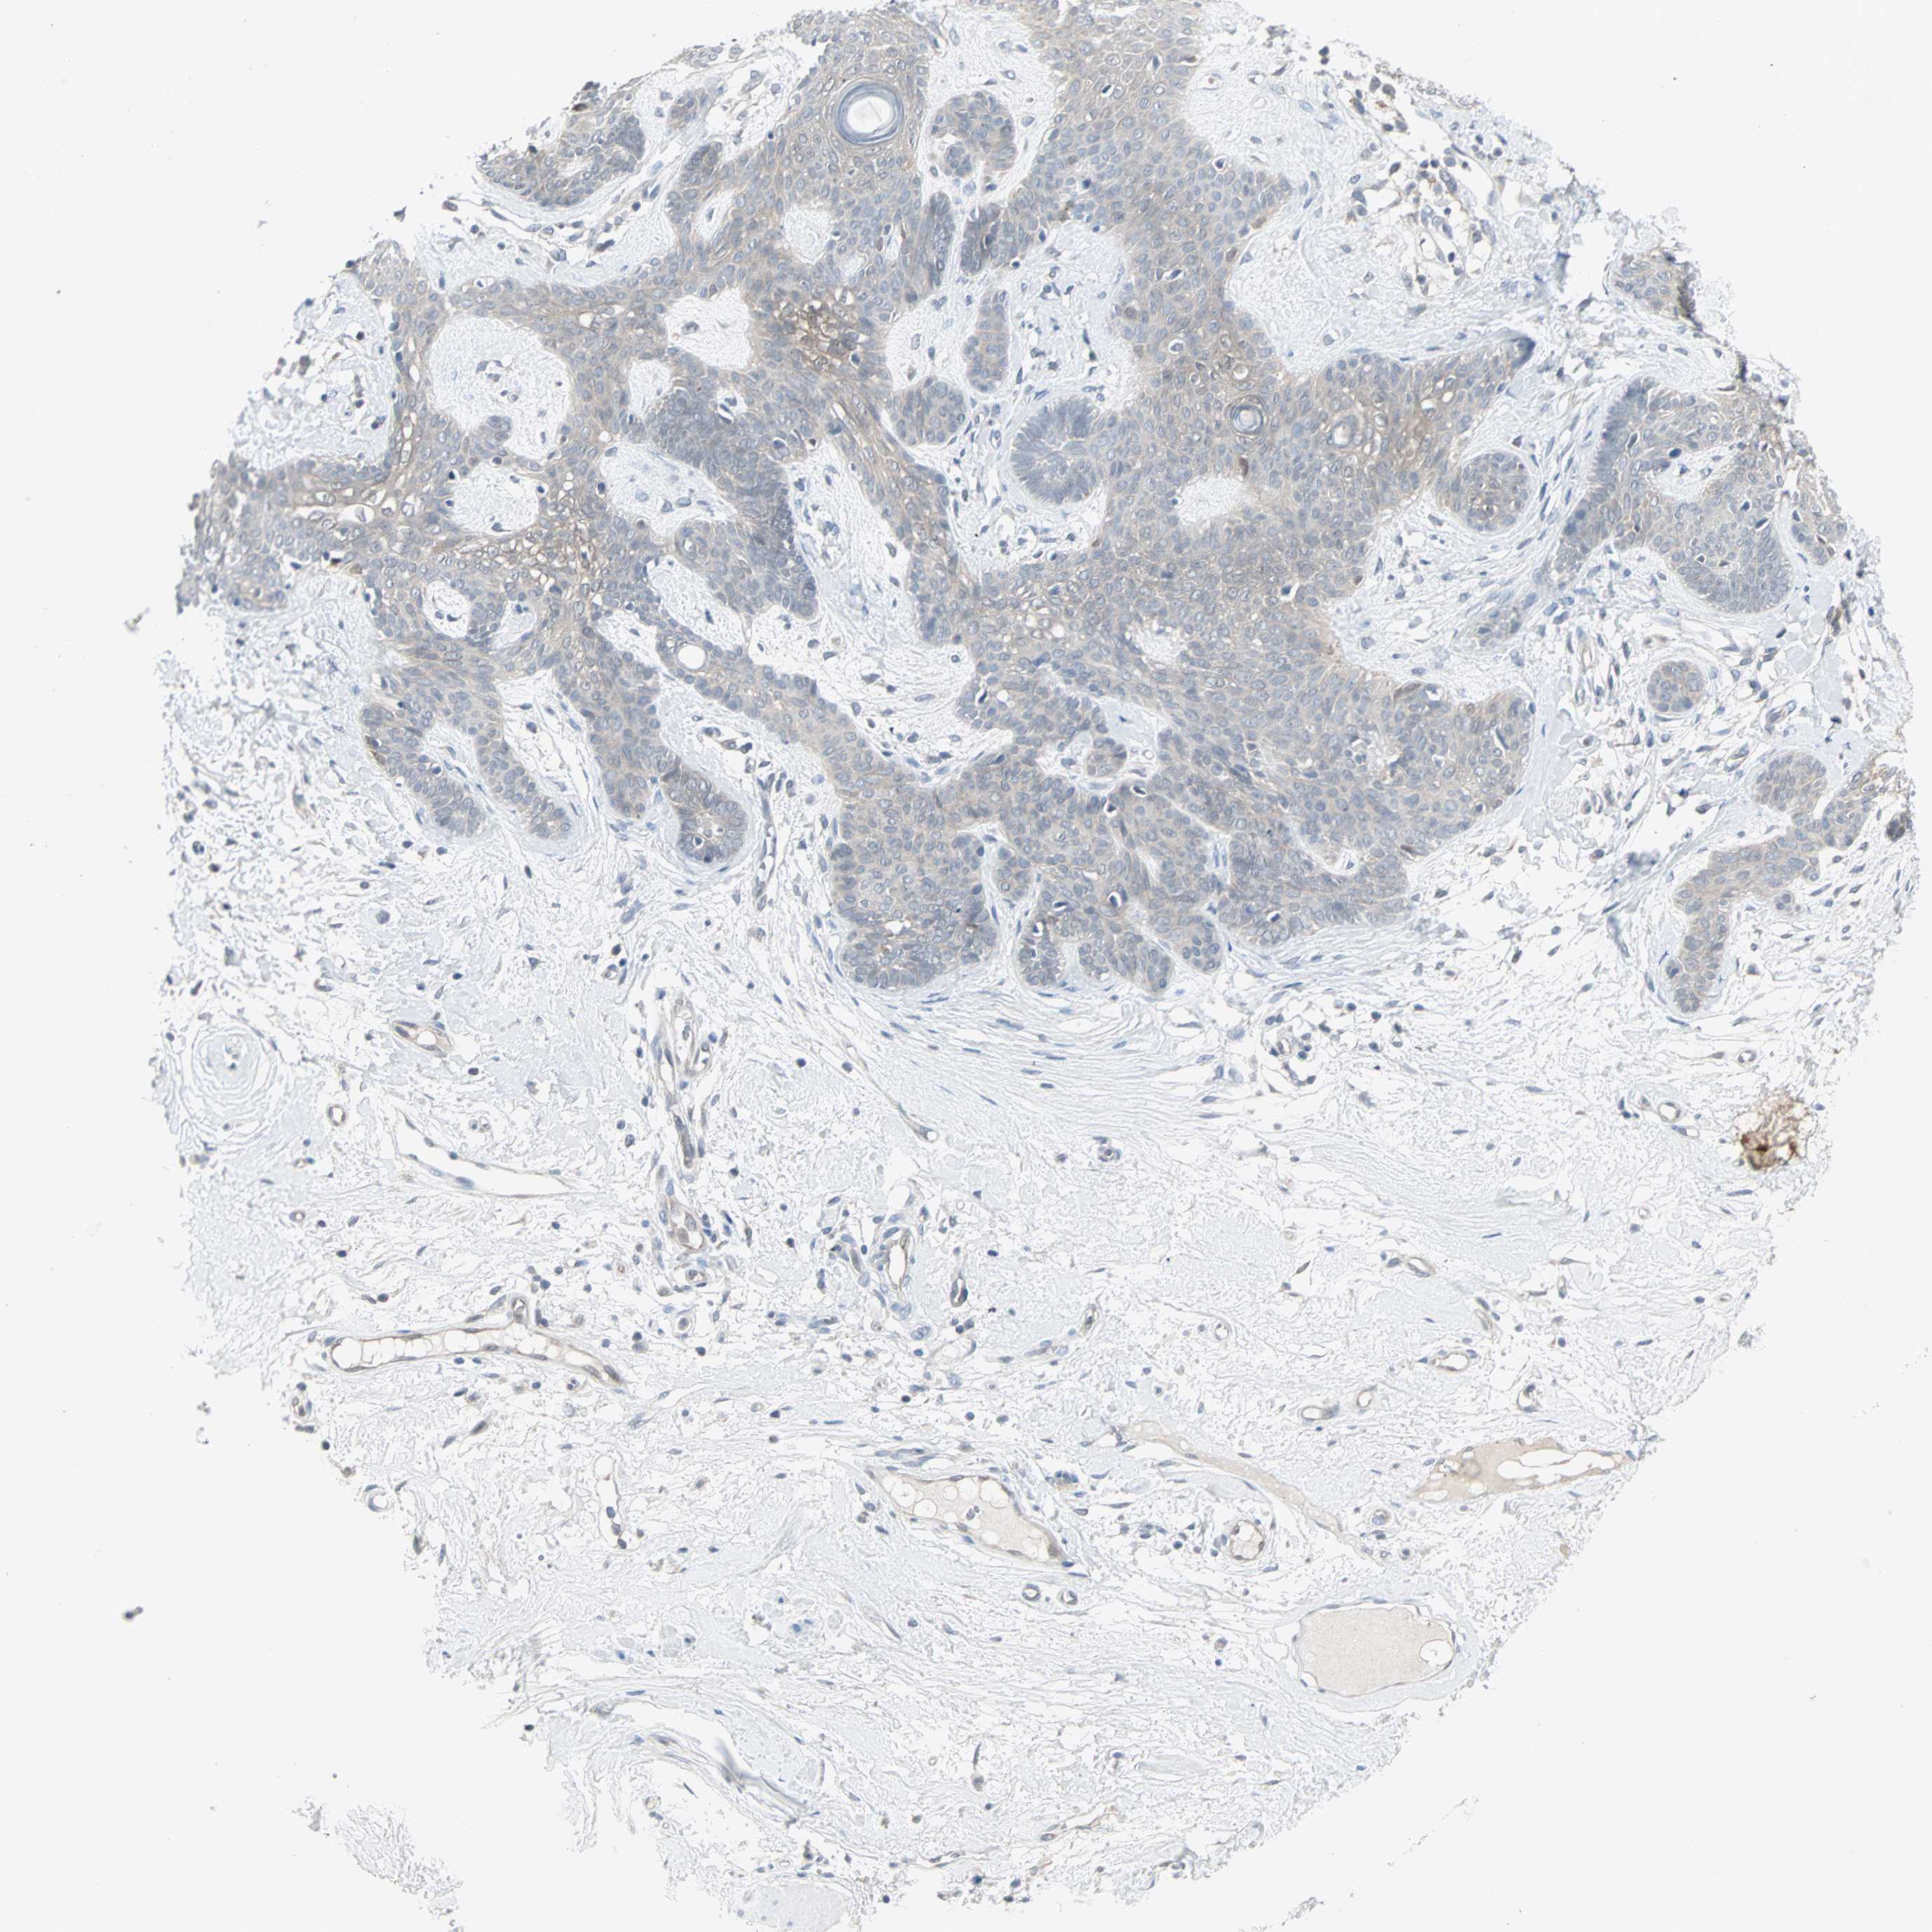

SKIN CANCER - Protein expressioni

A mouse-over function shows sample information and annotation data. Click on an image to view it in a full screen mode. Samples can be filtered based on level of antibody staining by selecting one or several of the following categories: high, medium, low and not detected. The assay and annotation is described here.

Each image is clickable and will lead to virtual microscopy that enables deeper exploration of all samples and also displays staining intensity scores, fraction scores and subcellular localization as well as patient and tissue information for each sample.

HPA005695

Squamous cell carcinoma, NOS